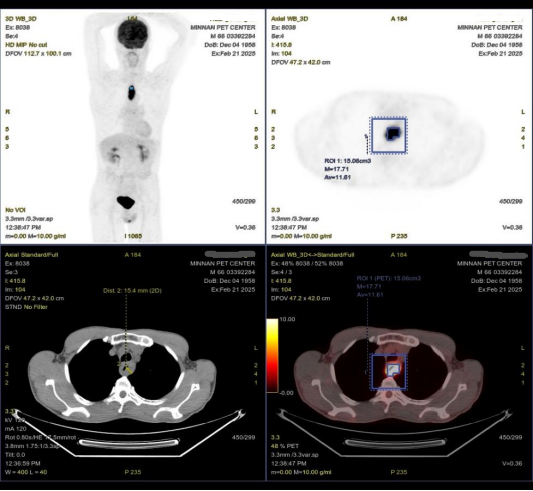

PET/CT(2025年2月21日):1.胸上段食管壁增厚、管腔狭窄,最厚处约1.5cm,累及范围约6.3cm,放射性摄取增高(SUVmax17.7)。2.双肺肺气肿;双肺散在炎性灶,左下肺为著;纵隔低代谢淋巴结,考虑炎性增生;动脉硬化。3.前列腺钙化灶;主动脉及冠脉管壁多发钙化。4.脊柱退行性变。

图片16.png图4 2025年2月21日PET/CT